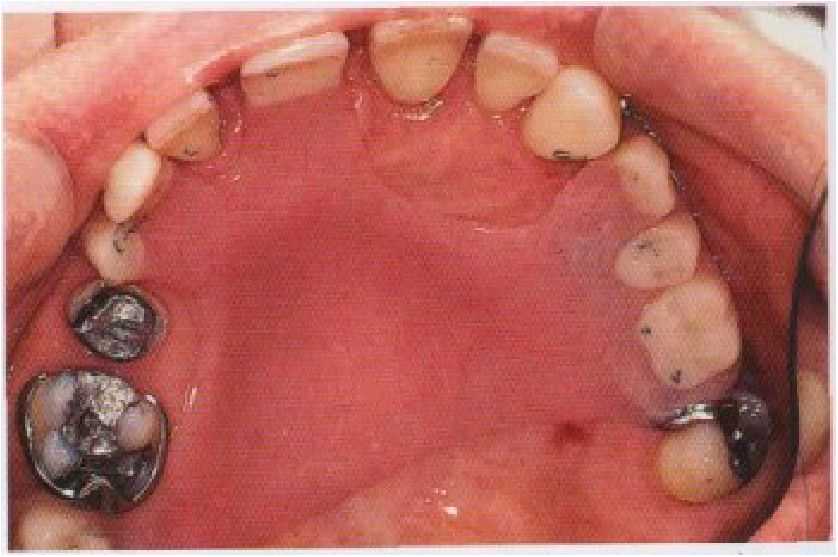

рис. 7-4. Временный частичный съемный протез верхней челюсти применен для сохранения удовлетворительных внешнего вида и окклюзии на период лечения тканей пародонта и восстановления боковых зубов.